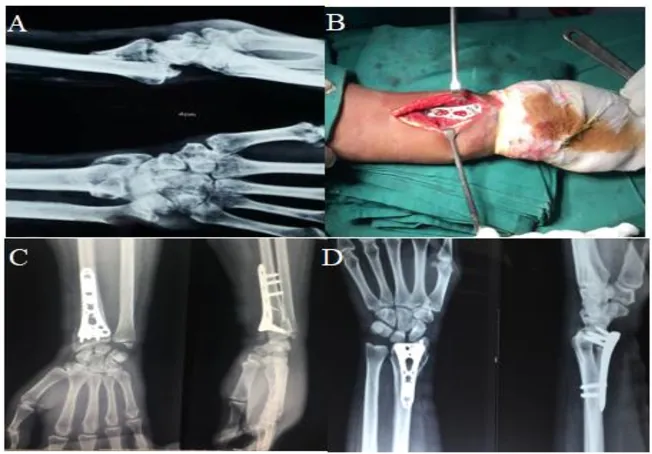

Ama-X-ray ajwayele ukusetshenziselwa ukuhlola ukuphuka nokuhlola izinga lokufuduka nokungazinzi. Izifundo zokucabanga ezengeziwe, ezifana nezikena ze-CT noma i-MRI, zingase zinconywe ukuze kutholwe ulwazi oluningiliziwe mayelana nephethini yokuphuka, ukubandakanyeka kwezicubu ezithambile, nekhwalithi yamathambo.

Ngesikhathi sokuhlinzwa, ukuphuka kuyavezwa, futhi izingcezu zamathambo zibuyiselwa endaweni yazo efanele. I ipuleti lokukhiya libe selibekwa phezu kwesayithi lokuphuka, futhi izikulufu zifakwa ngepuleti nasethanjeni ukuze kuzinzise ukuphuka. Uma ukuphuka sekulungiswe ngokuphephile, ukusika kuyavalwa, futhi inqubo yokutakula iqala.